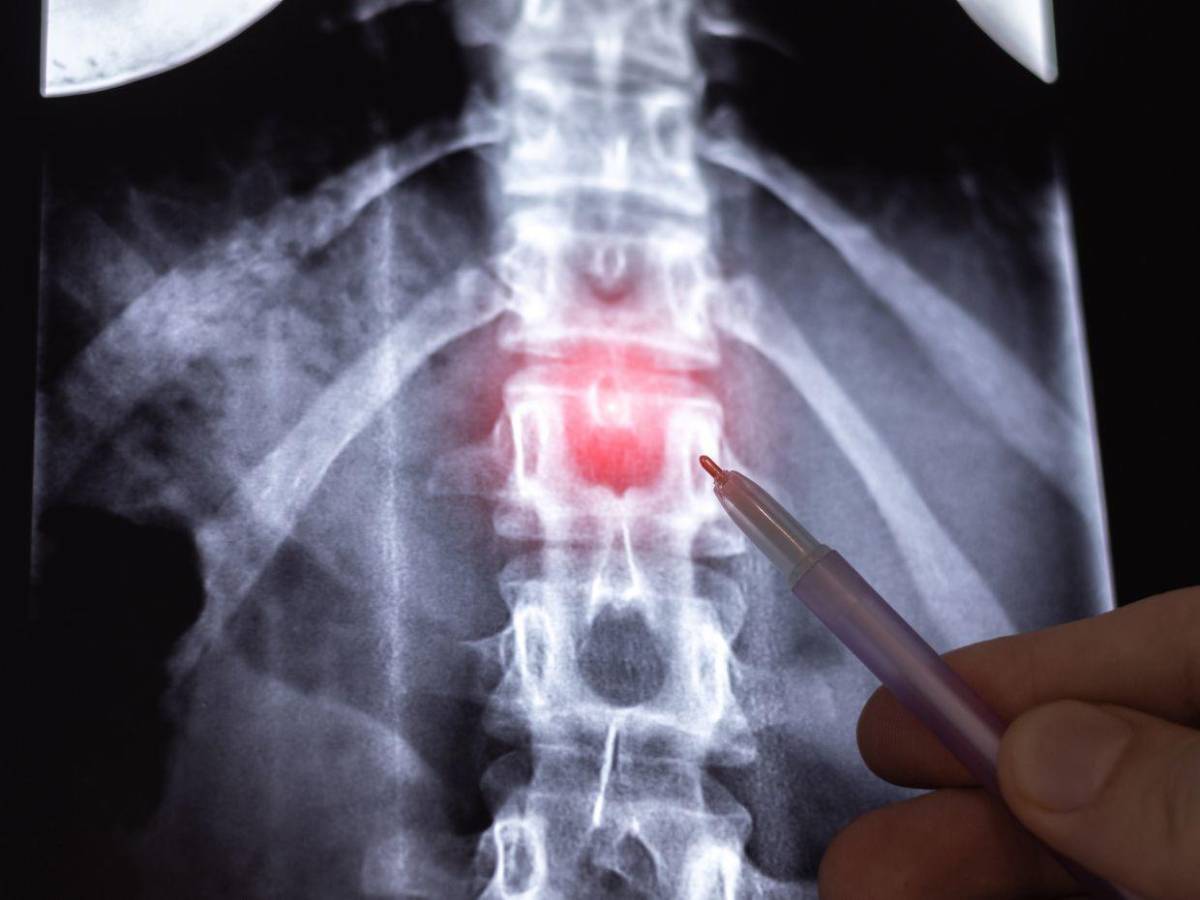

Otra de las lesiones características de la espalda es la hernia discal. “La columna vertebral es como un conjunto de bloques apilados. Entre cada uno de esos bloques hay unos discos que funcionan como amortiguadores. Imagínalos como si fueran los cojines de un sofá que te permiten moverte y doblarte sin que los huesos se rocen entre sí. Ahora bien, en ocasiones, estos discos pueden sufrir un deslizamiento o una ruptura y eso es lo que se conoce como hernia discal”, aclara el fisioterapeuta.

Sus causas más comunes tienen que ver con el desgaste natural del cuerpo debido a la edad. “A medida que vamos cumpliendo años, nuestros discos se van deshidratando y perdiendo flexibilidad, lo que facilita un desgarro o un desplazamiento. Además, hay actividades o hábitos que pueden incrementar las probabilidades de sufrir una hernia discal: movimientos repetitivos de torsión sin control o levantar objetos pesados sin la técnica adecuada”, comenta.